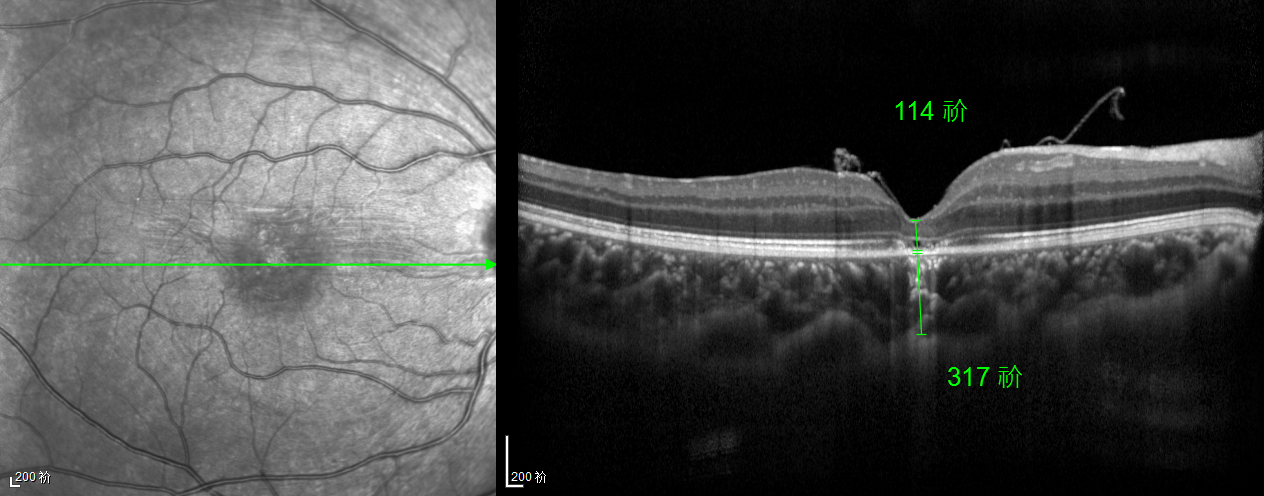

除此之外,利用自體組織覆蓋為黃斑裂孔提供了理想的愈合環(huán)境,裂孔閉合速度顯著快于傳統(tǒng)方法。誠(chéng)誠(chéng)接受手術(shù)24小時(shí)后,檢查可見(jiàn)內(nèi)界膜瓣位置良好;術(shù)后1個(gè)月,黃斑裂孔已經(jīng)閉合,視力恢復(fù)到0.5;術(shù)后兩個(gè)月,視力進(jìn)一步提升到0.7。